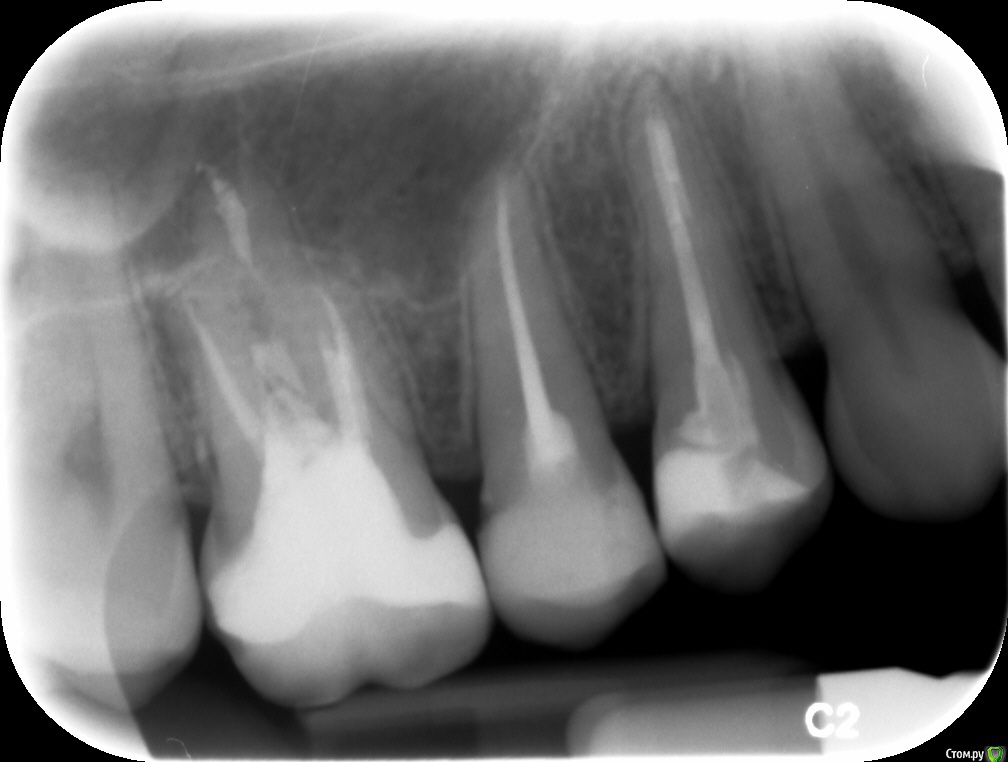

Здравствуйте. Подскажите пожалуйста,как выглядят зубы после лечения? Было две кисты .как правильно считать зубы не знаю.верхние правые 4 и 6

post-49942-0-10715600-1526574748_thumb.jpg